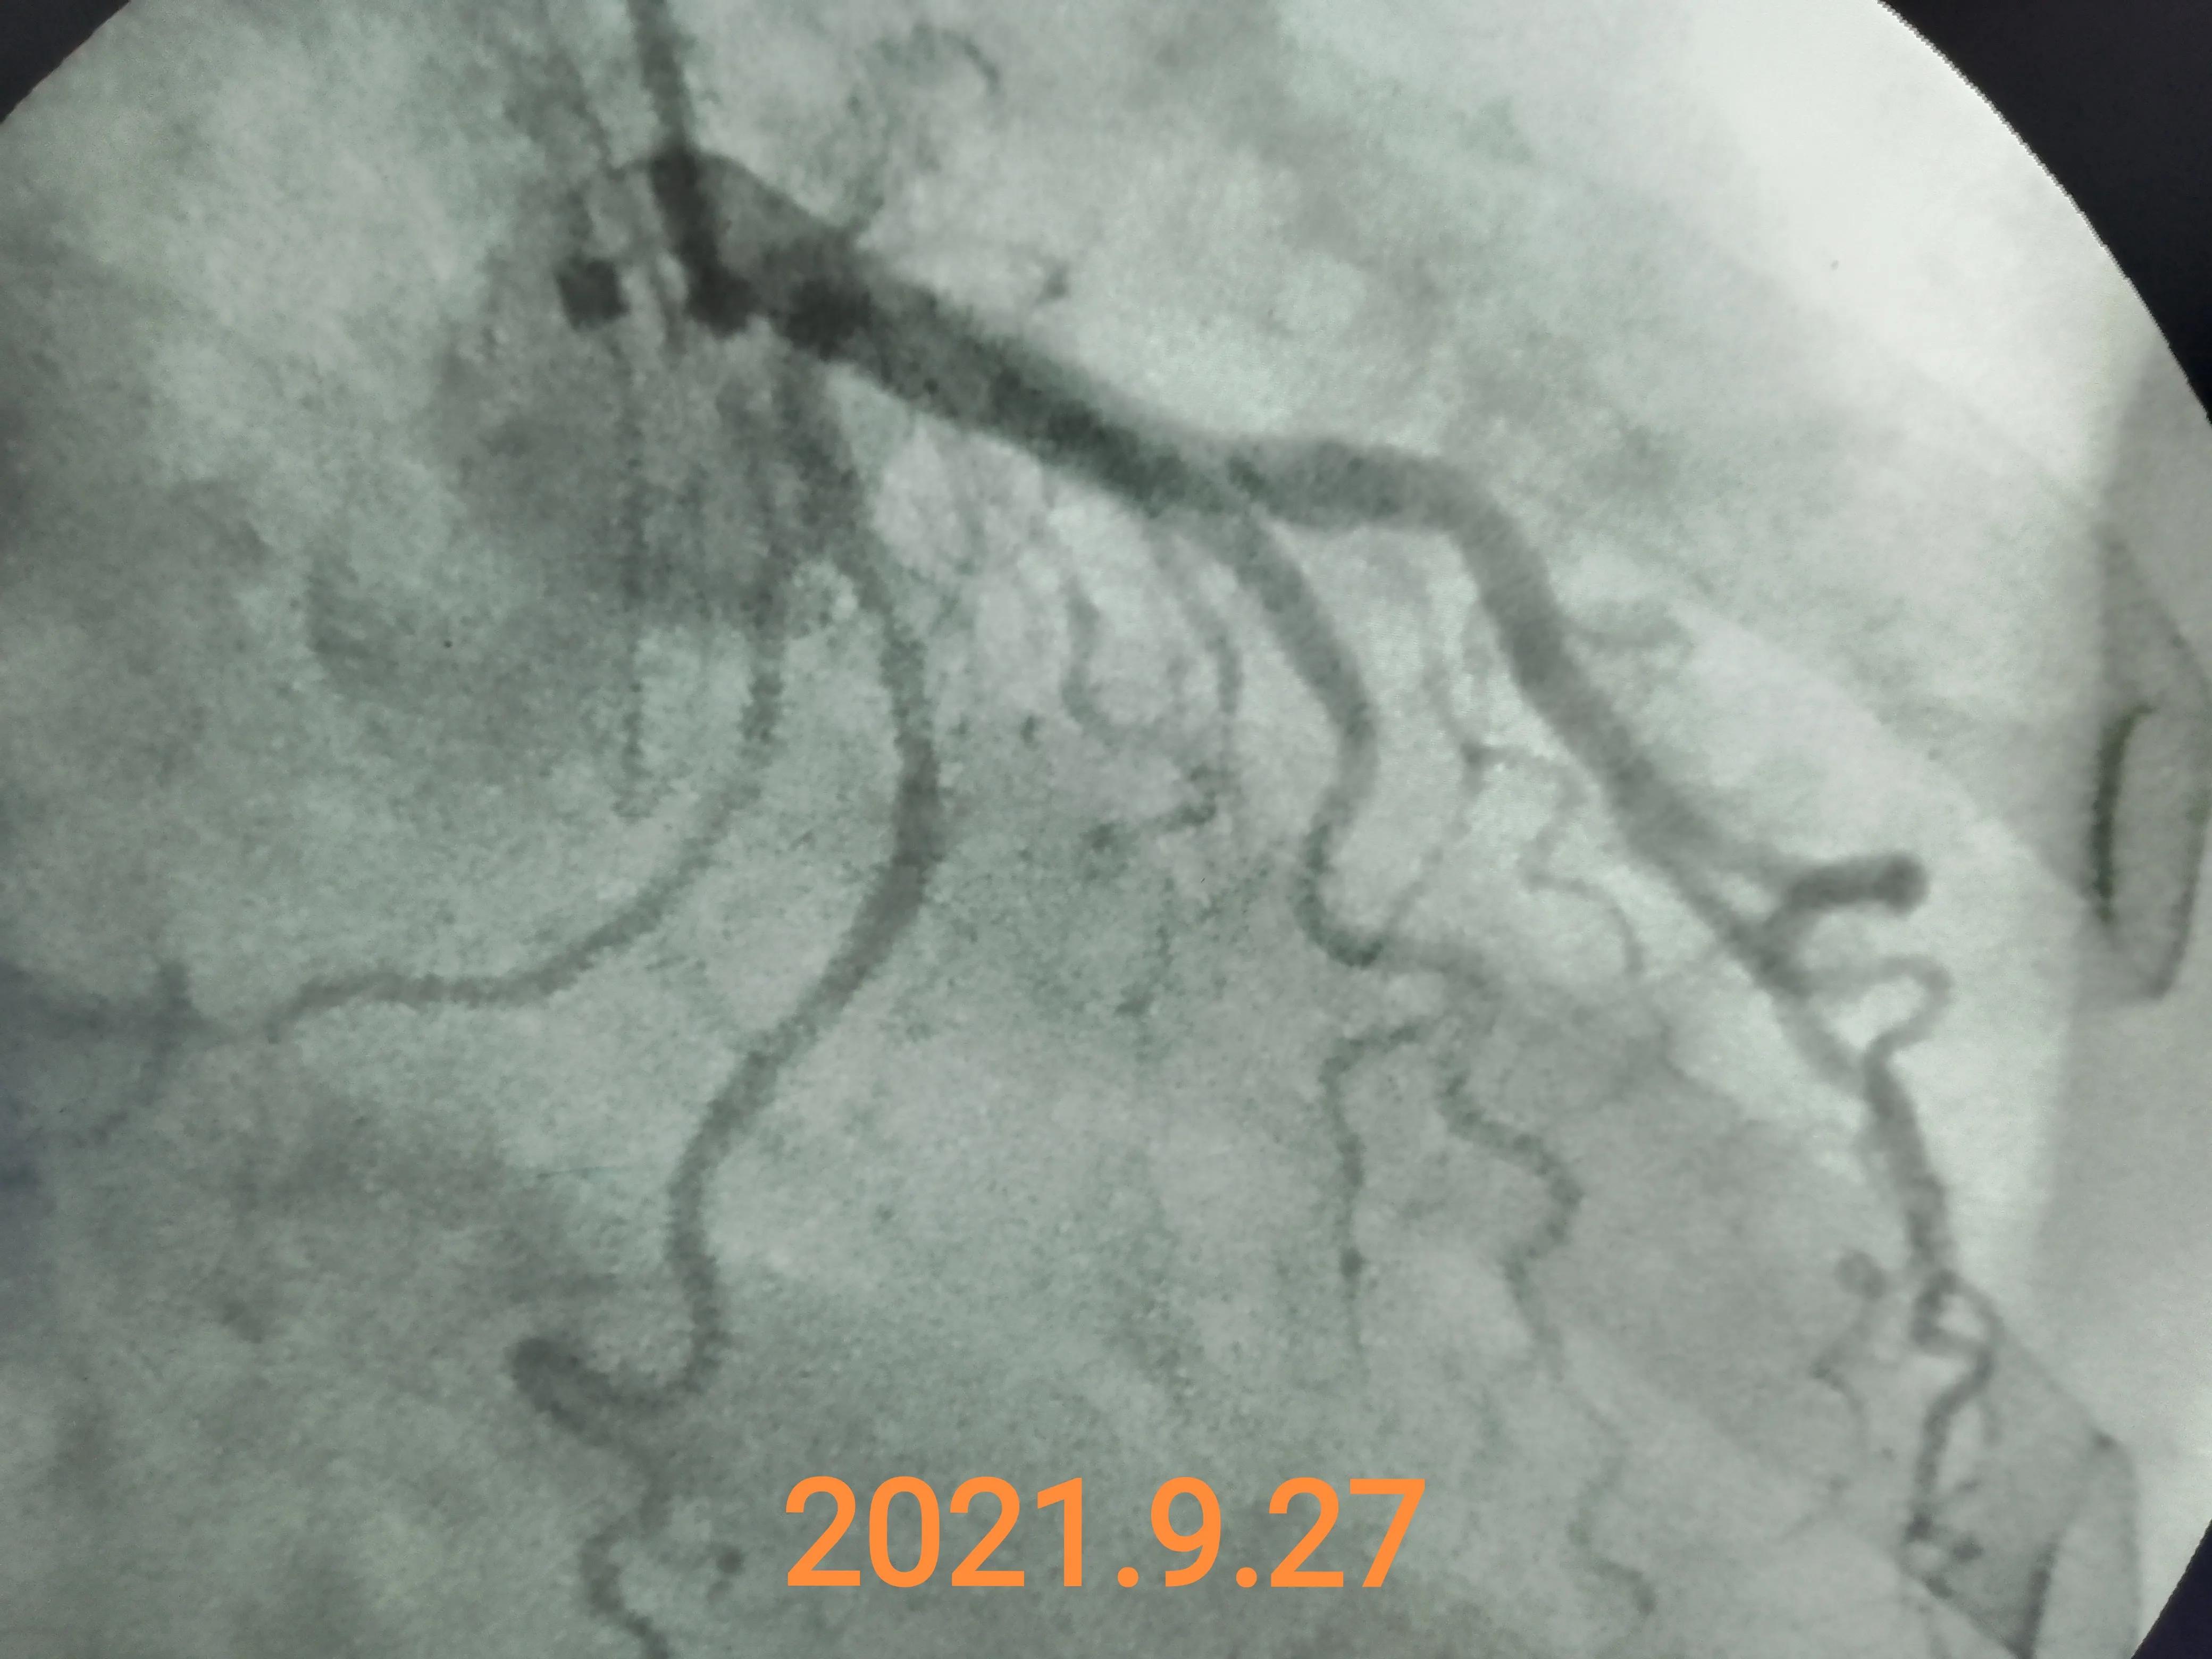

做了冠脉造影排除了冠脉明显狭窄